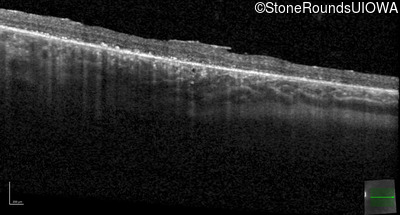

Optical Coherence Tomography - Right - 20/50

Exemplar / OCT Stack

OCT Stack